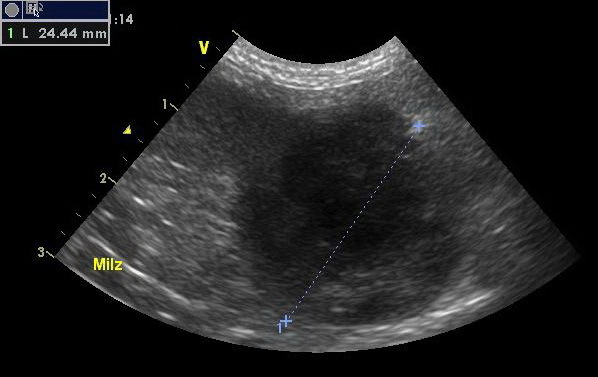

Um die Ursache zu ergründen, wurde bei Lisa eine Ultraschalluntersuchung des Bauchraumes durchgeführt. Hierzu wird der Patient mit dem Rücken in eine weiche kuhlenförmige Matte gelegt, der Bauch geschoren, mit Ultraschallgel bestrichen und mit verschiedenen Sonden „abgefahren“. Leider sind die Veränderungen, die wir im Bauchraum von Lisa finden, gar nicht schön: so ist in der Milz ein Tumor, der alsbald die Größe einer Faust hat. Darüber hinaus ist die gesamte Leber von Tumoren durchsetzt, und so kommt eine eventuelle chirurgische Hilfe für die kleine Hündin leider zu spät.